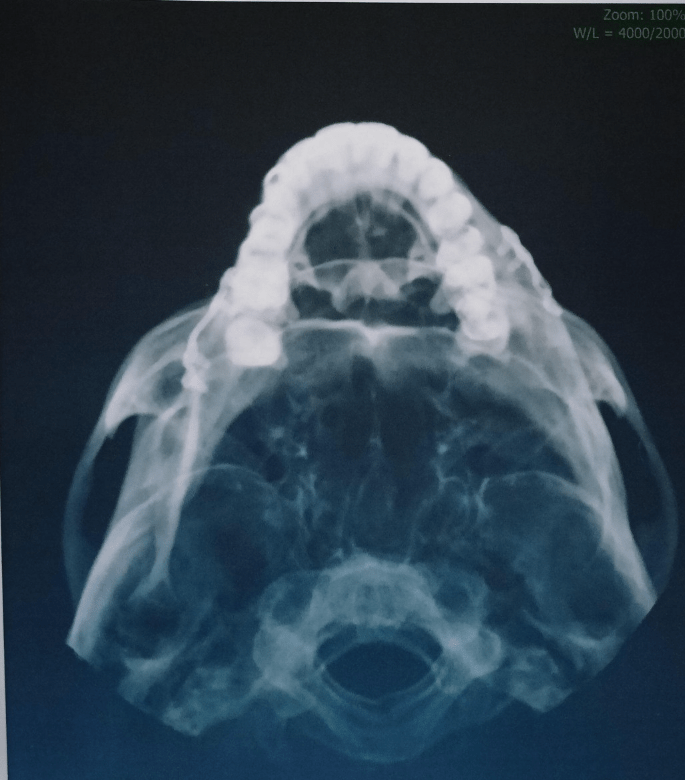

Integrazione della QMR Therapy nel recupero post-operatorio maxillo-facciale

Quadro clinico: Il paziente si è rivolto al nostro studio dopo un intervento di chirurgia maxillo-facciale. Presentava gonfiore persistente, tensione dei tessuti, difficoltà nei movimenti mandibolari e un generale senso di rigidità nell’area trattata chirurgicamente.

Trattamento terapeutico – QMR Therapy: è stato programmato un percorso con QMR Therapy come supporto al recupero post-operatorio, con l’obiettivo di favorire una migliore gestione dei tessuti, ridurre la tensione e facilitare la mobilità dell’area maxillo-facciale.

Nelle sedute successive si è osservata una progressiva normalizzazione dei tessuti peri-mastici, un miglioramento della mobilità e una riduzione del gonfiore residuo, confermati sia dal paziente sia dalla valutazione manuale.